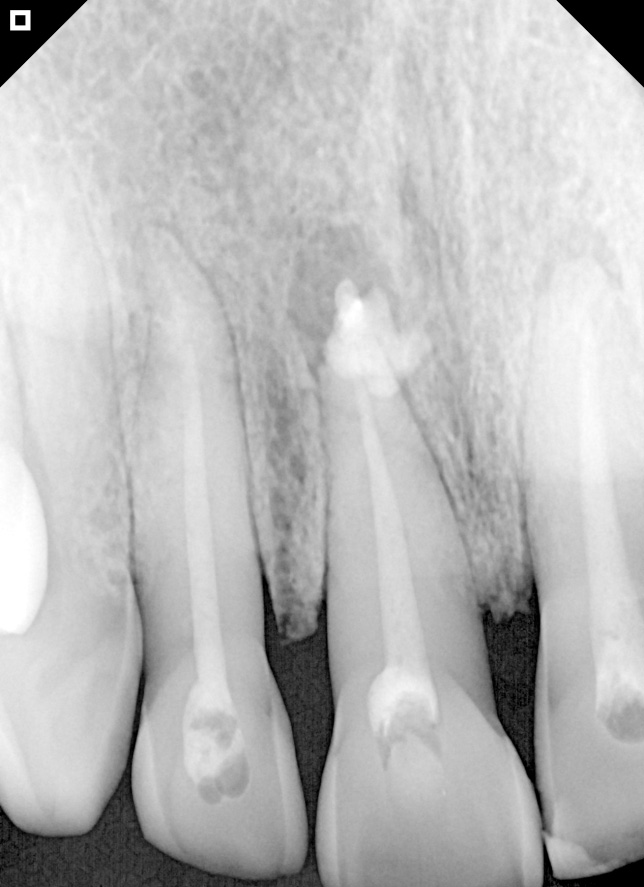

Radiography immediately after application of Bio-C Temp.